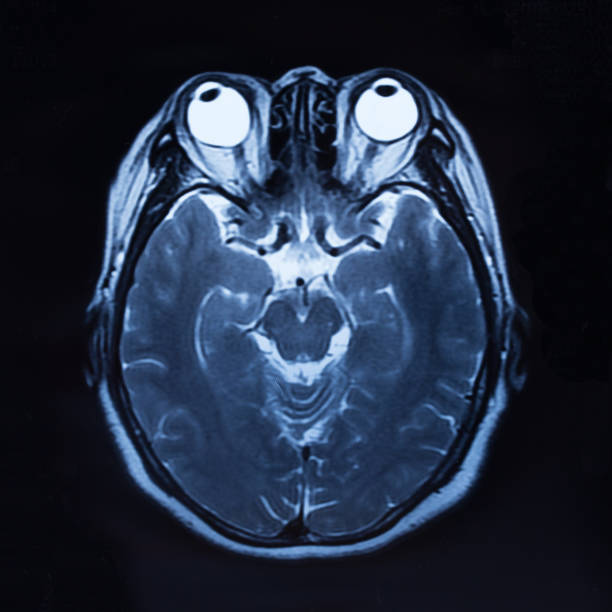

고혈압은 뇌출혈의 가장 큰 원인으로 볼 수 있는데 고혈압 환자라면 혈압이 갑작스럽게 상승하는데 이 때 산소와 영양소가 뇌로 들어가는 통로인 혈관에 변화를 일으키는데 혈관이 버티지 못하고 터지게 됩니다. 뇌동정맥의 기형에 의한 뇌출혈, 뇌동맥류 파열에 의하여 나타나며 잦은 흡연이나 다른 질병의 합병증으로 인해 발생할 수 있으며 뇌손상은 팔, 다리, 심하면 얼굴등 신체 일부분이 평생 마비시키며, 골든타임을 놓칠 경우 사망할 수도 있어 뇌출혈 전조증상에 대해 알고 있는 것이 좋습니다.

뇌출혈 전조증상 세 번째는 시력과 균형감각의 상실을 이야기 할 수 있습니다. 뇌 혈관 문제로 생기는 뇌출혈은 시신경과 관련하여 시야가 흐려지고 눈을 정상적으로 뜨기 어렵기 때문에 시력을 이부 상실할 수 있으며 균형 감각도 둔해져 가만히 있더라도 몸이 계속 기울어져 넘어질 수 있습니다.